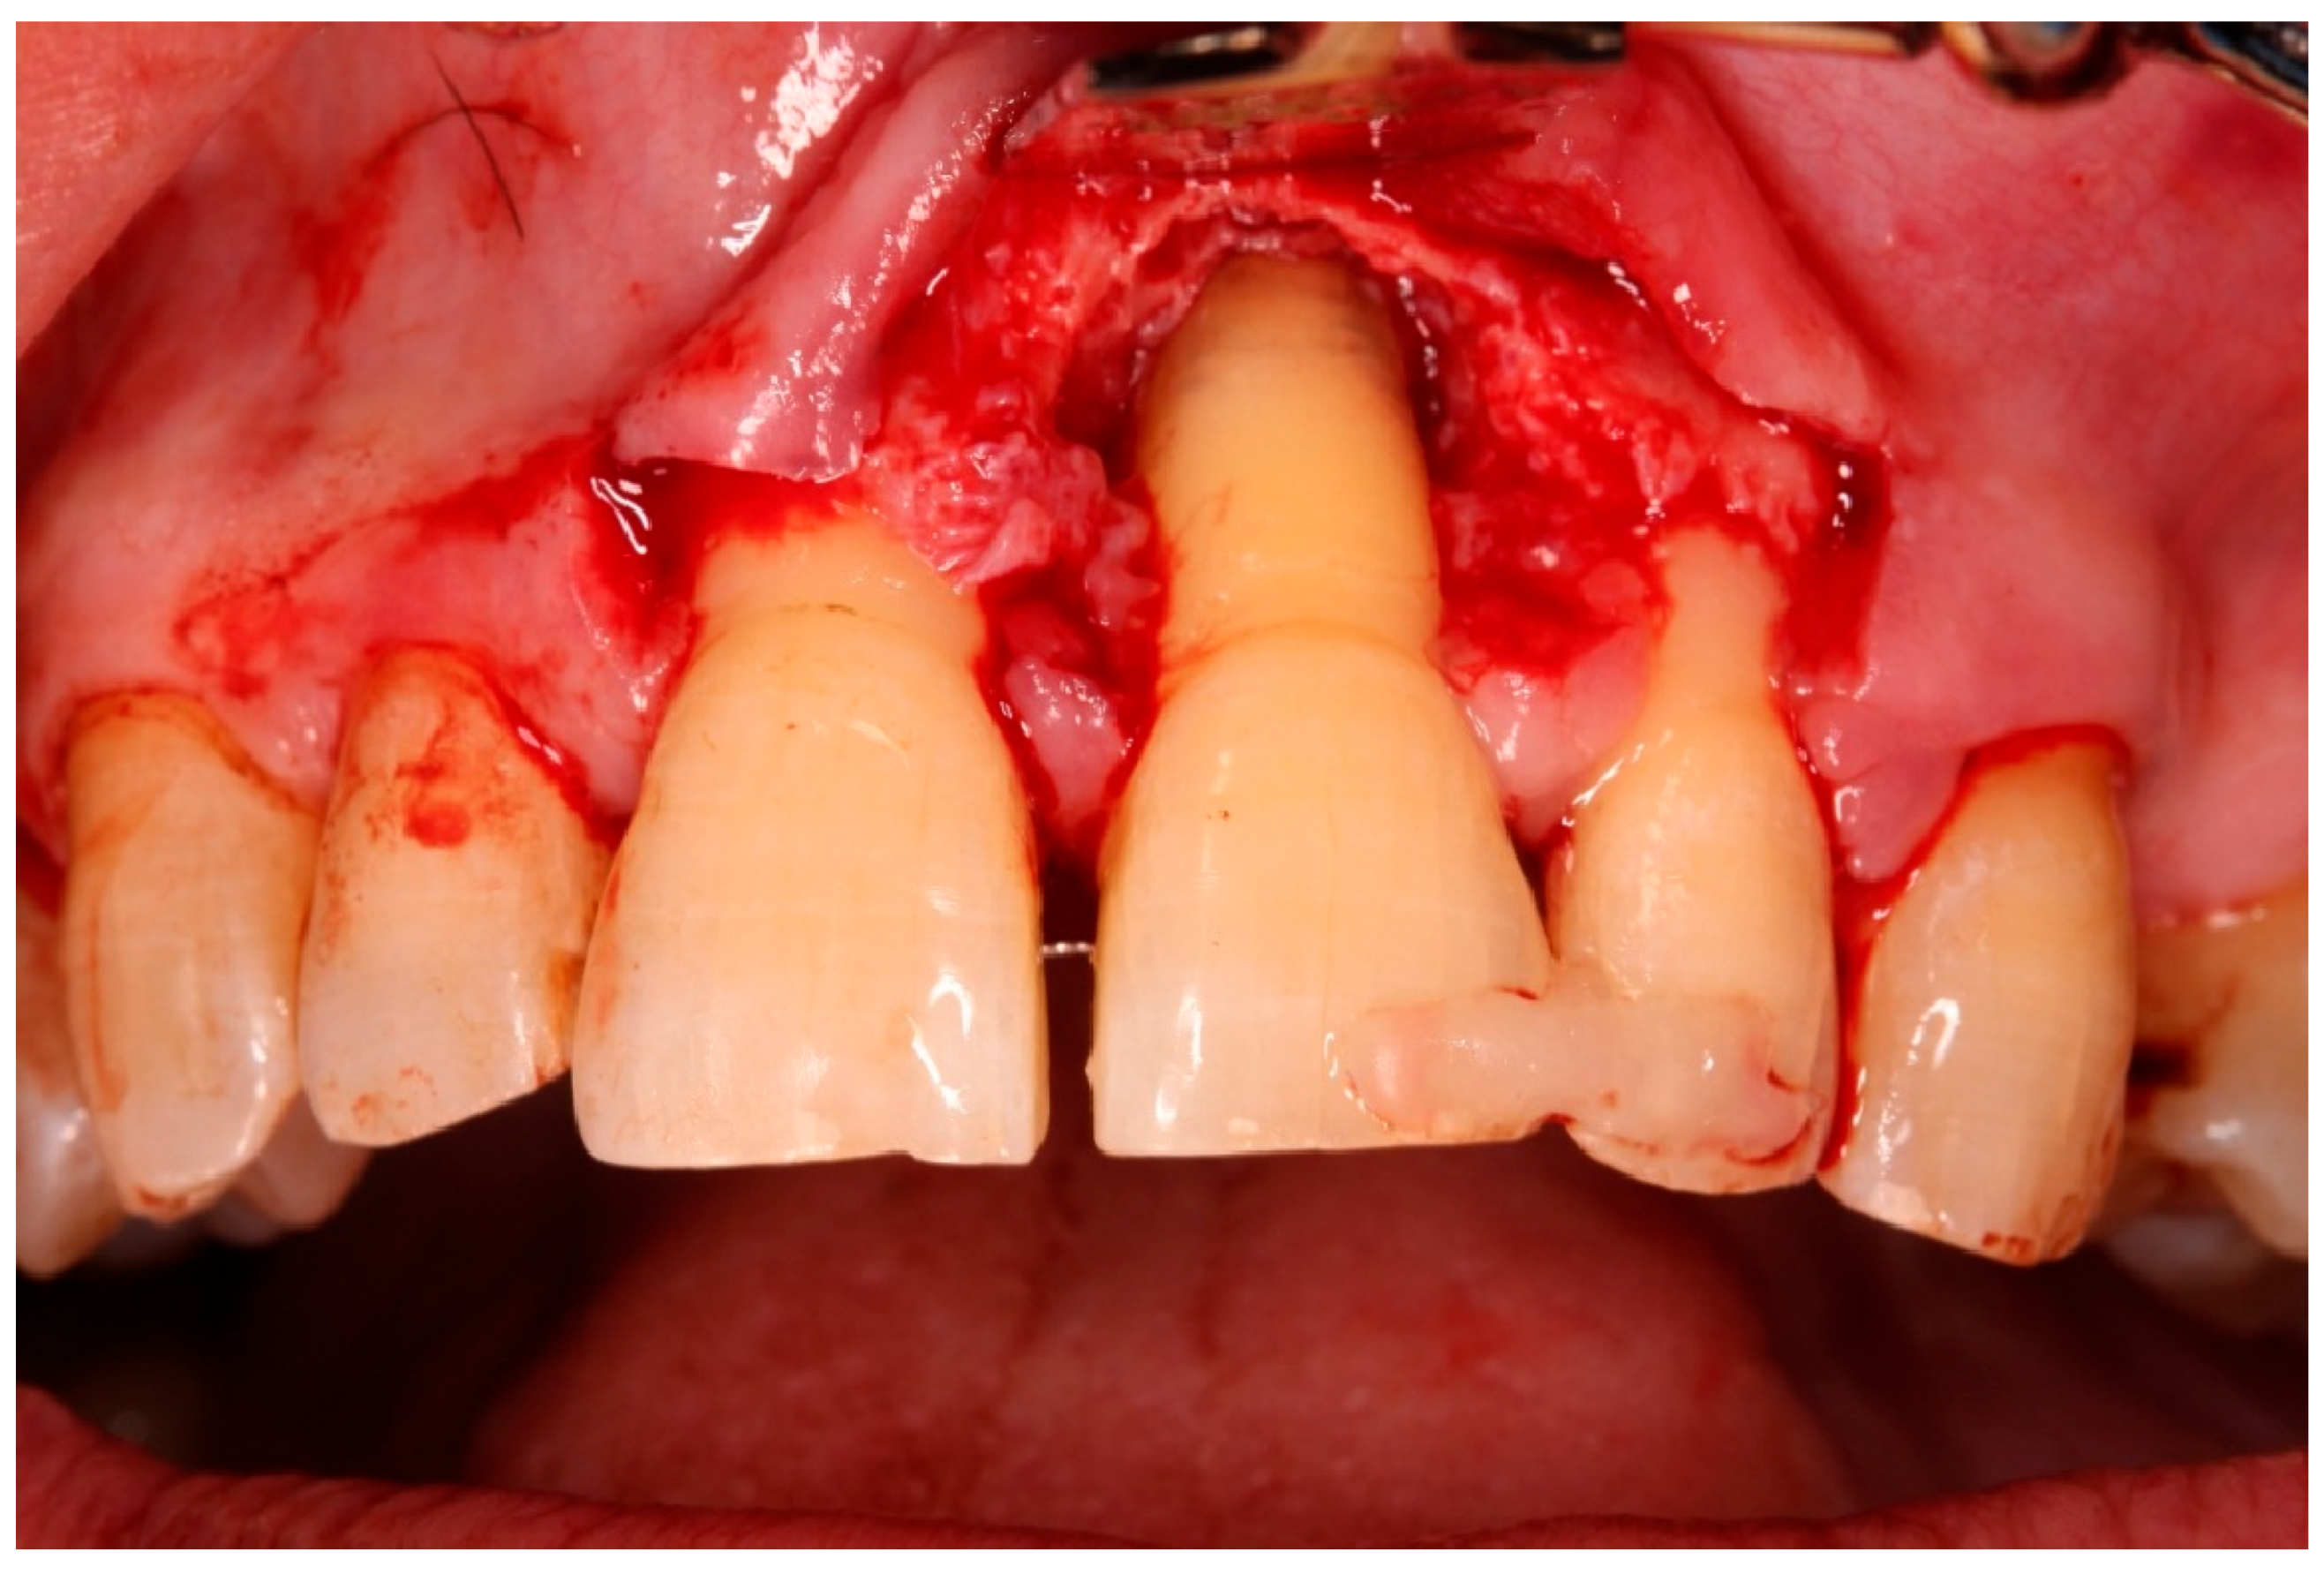

- Guided tissue regeneration: A full-thickness flap was elevated to expose the defect morphology. Autologous bone chips collected during drilling were combined with xenograft particles (Bio-Oss®, Geistlich Pharma, Wolhusen, Switzerland) and enamel matrix derivative (Emdogain®, Straumann, Basel, Switzerland) and placed around the replanted root. A resorbable collagen membrane (Bio-Gide®, Geistlich Pharma, Wolhusen, Switzerland) was positioned to stabilize the grafted area and support space maintenance. The flap was repositioned and sutured to achieve primary closure.